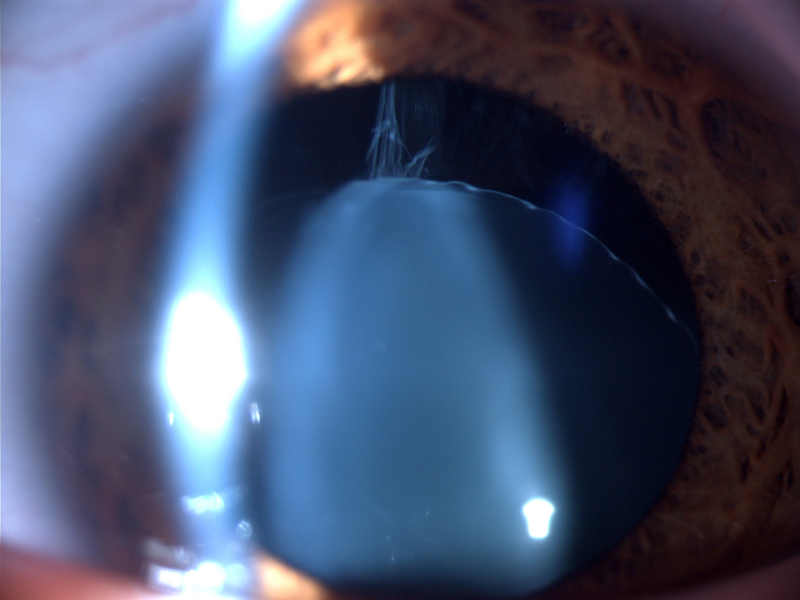

Niña de 13 años, con 49,4kg de peso, 1,63 m de talla y 18,59 kg/m2 de índice de masa corporal. Derivada por el pediatra para valoración oftalmológica, por antecedentes familiares de homocistinuria (hermano) y sospecha de Síndrome de Marfan (hermana). A la exploración física se destaca el aspecto marfanoide y se objetiva una agudeza visual corregida (OD: 160°-3.50-9.25; OI: 180°-3.50-9.25) de 0,6 en ambos ojos. En lámpara de hendidura se observa una subluxación inferior del cristalino bilateral y fondo de ojo dentro de la normalidad.1. ¿Cuál es la primera sospecha diagnóstica?

La luxación o ectopia del cristalino, es el signo oftalmológico más llamativo y está presente en aproximadamente un tercio de los pacientes en la primera década de la vida y en más del 90% de los pacientes en la tercera década1,2.Se define por el desplazamiento del mismo, normalmente hacia inferior nasal de forma simétrica, como resultado de la degeneración y rotura de las fibras de la zónula. Esto puede provocar disminución de la agudeza visual o incluso glaucoma agudo secundario2. La fibrilina-1 (glucoproteína secretada en la matriz extracelular) es uno de los componentes más importantes de las fibras zonulares del cristalino con proteínas ricas en cisteína. En la homocistinuria la estructura de la fibrilina se altera por la reducción de uniones disulfuro en la C-terminal de la fibrilina-13.